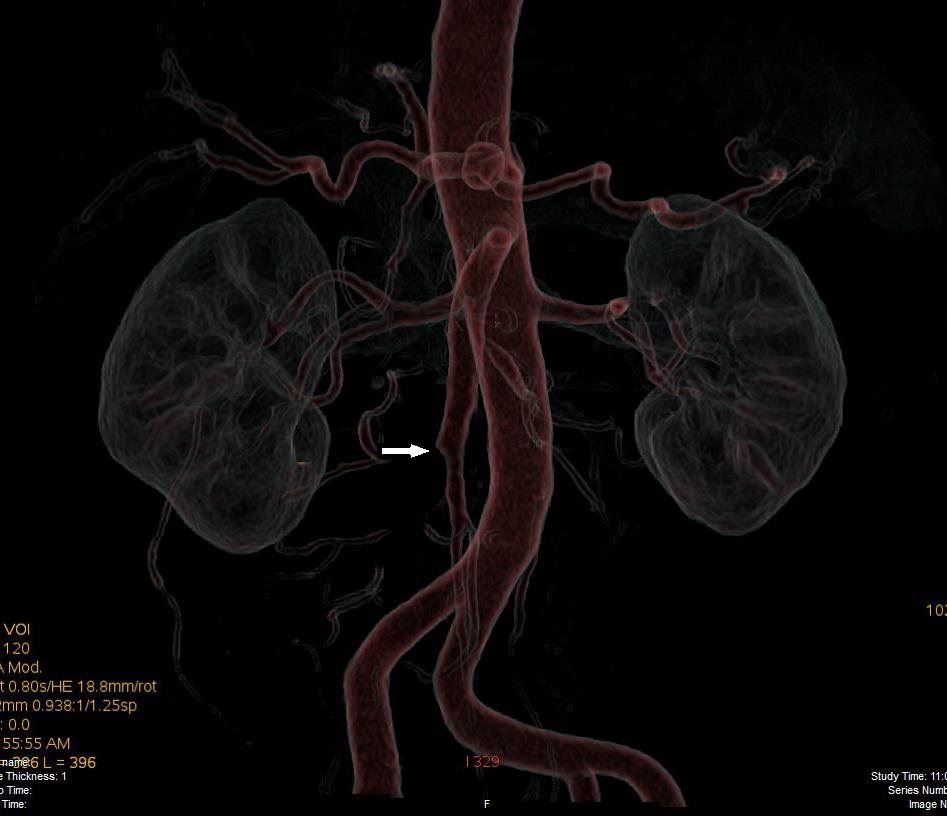

Acute abdominal pain is one of the most common conditions encountered in the emergency department. The differential diagnosis of acute abdominal pain is extensive and identifying the underlying etiology can be challenging. We report a case of acute transient ischemic jejunitis due to symptomatic isolated superior mesenteric artery dissection in a patient with no cardiovascular risk factors or autoimmune diseases. Symptomatic isolated superior mesenteric artery dissection is a rare cause of acute abdominal pain usually treated in the surgical department. The patient had criteria for conservative treatment and rapidly recovered. We highlight a rare condition which should be taken into account for the differential diagnosis of acute abdominal pain.